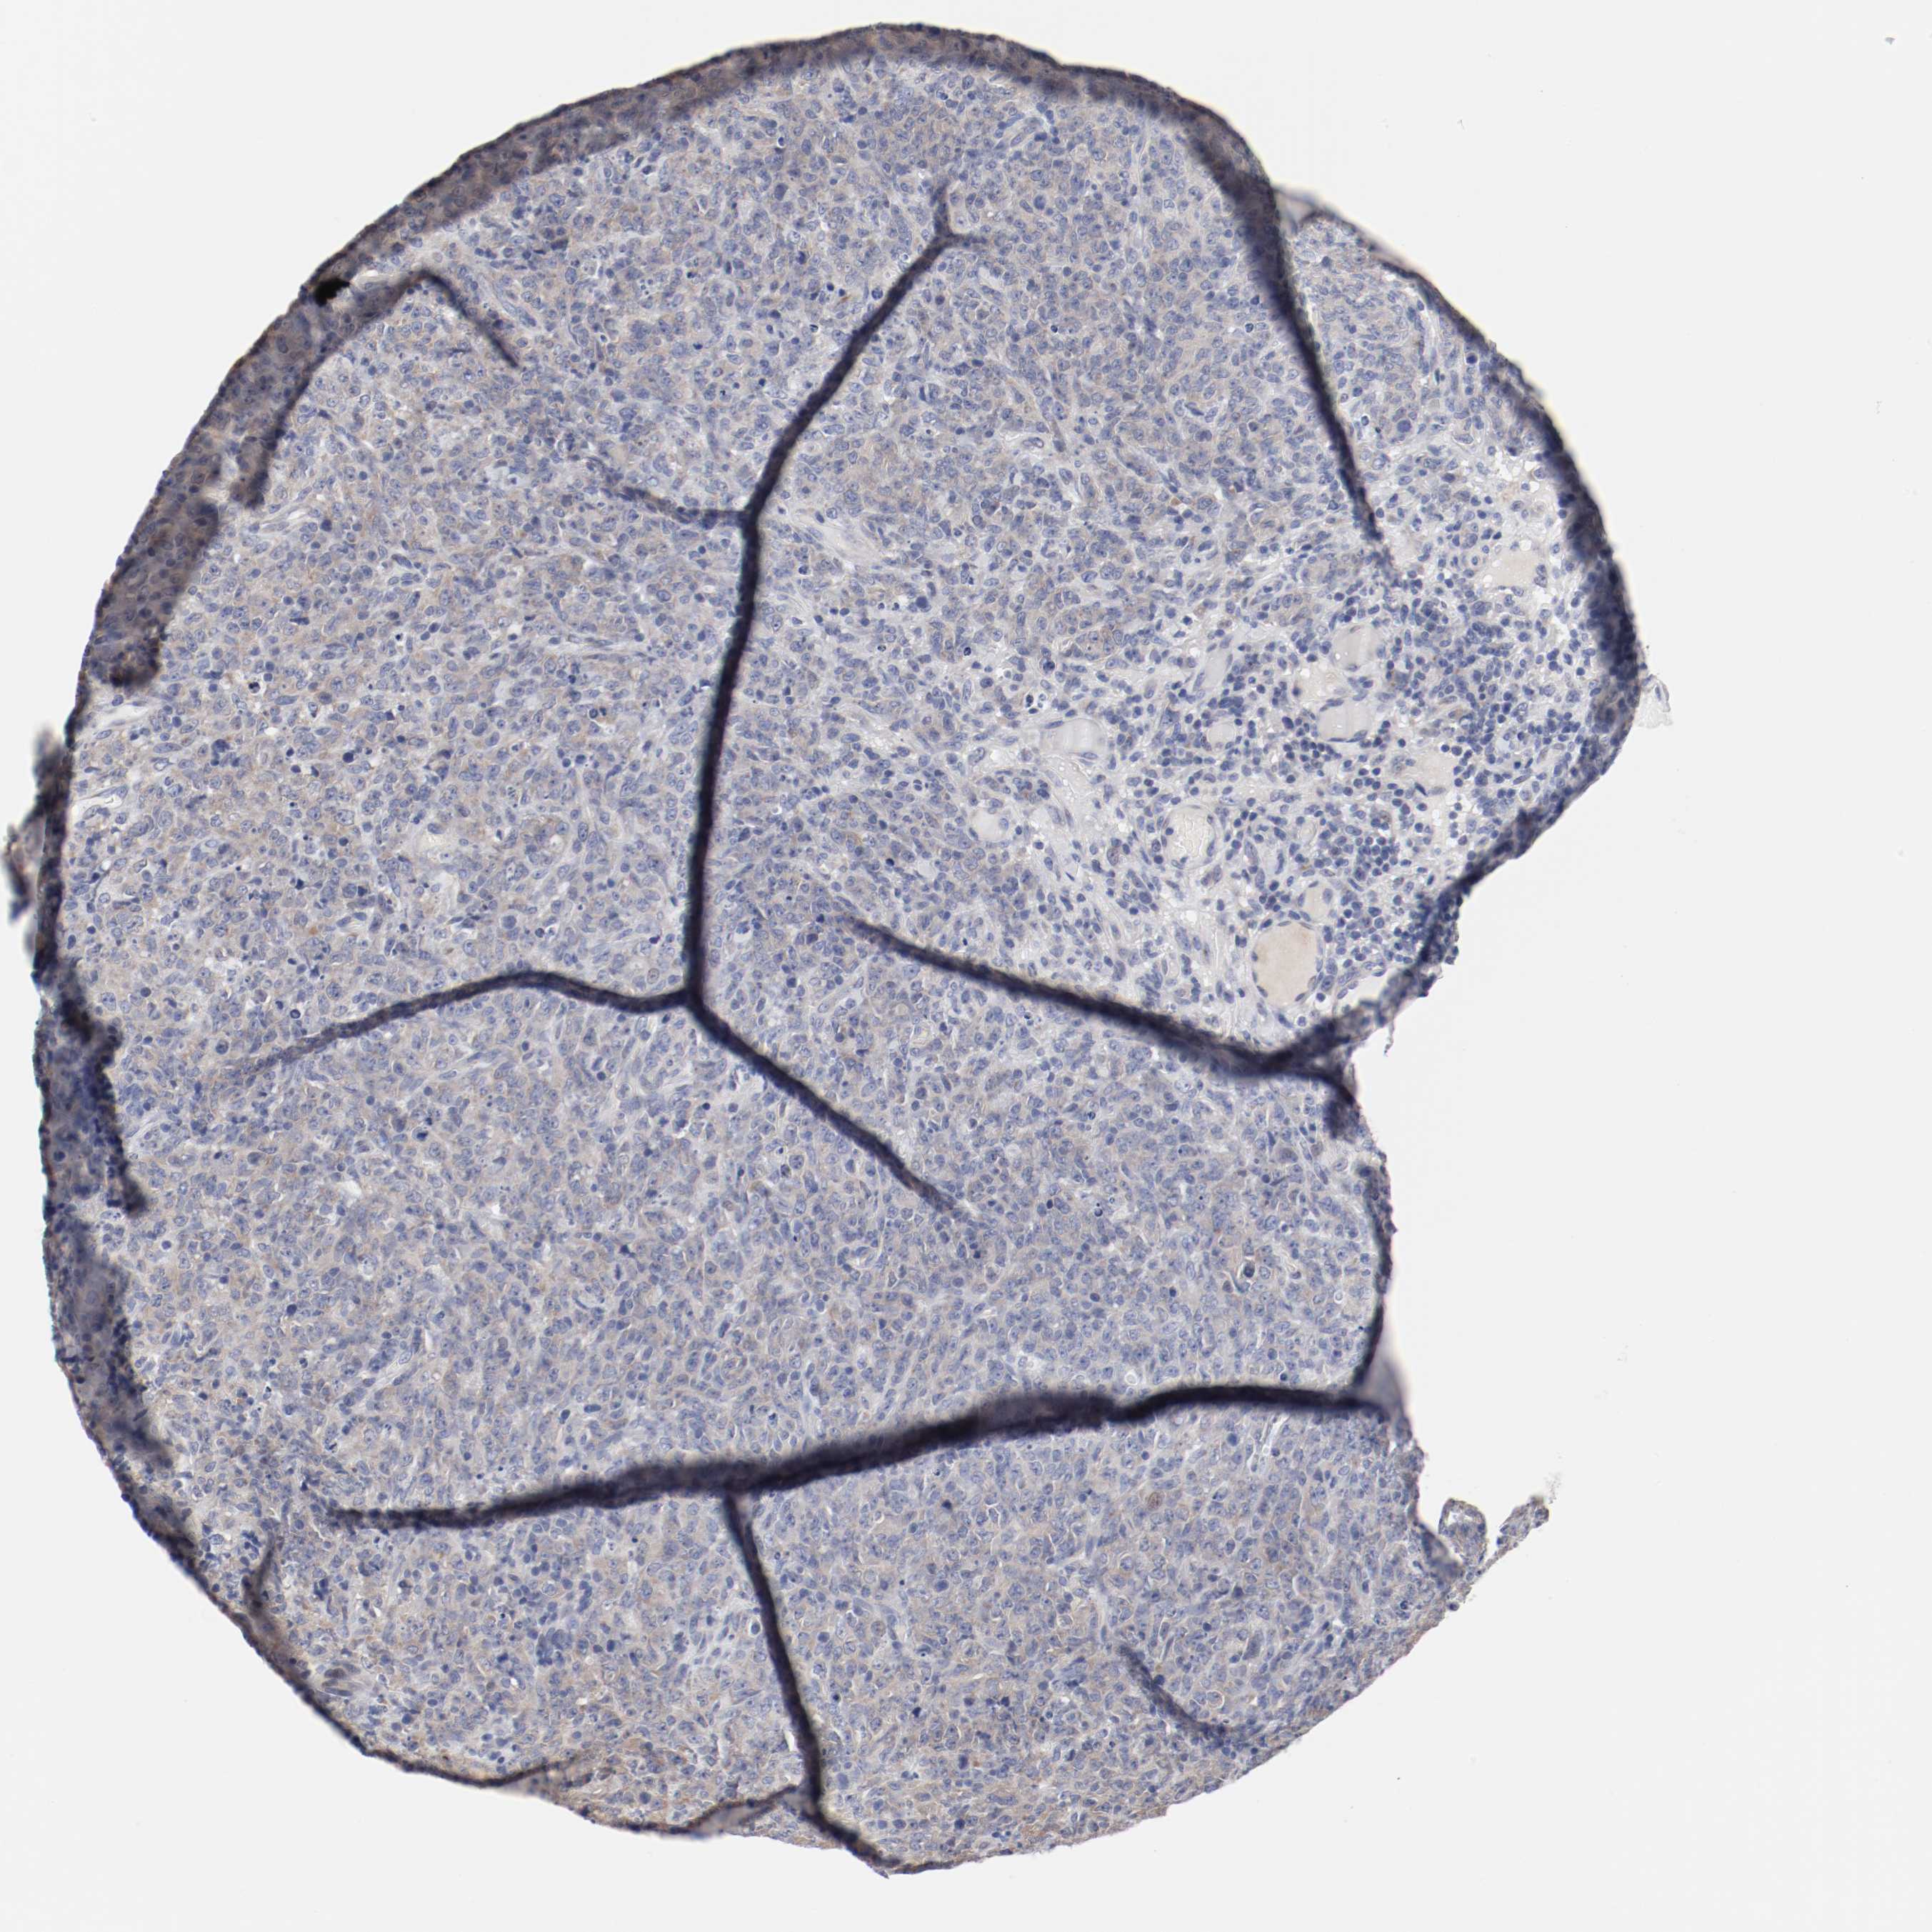

CANCER LYMPHOMA Show tissue menu

LYMPHOMA - Protein expressioni

A mouse-over function shows sample information and annotation data. Click on an image to view it in a full screen mode. Samples can be filtered based on level of antibody staining by selecting one or several of the following categories: high, medium, low and not detected. The assay and annotation is described here.

Each image is clickable and will lead to virtual microscopy that enables deeper exploration of all samples and also displays staining intensity scores, fraction scores and subcellular localization as well as patient and tissue information for each sample.

Antibody HPA003648

Staining

High

Medium

Low

Not detected

Intensity

Strong

Moderate

Weak

Negative

Quantity

>75%

75%-25%

<25%

None

Location

Nuclear

Cytoplasmic/membranous

Cytoplasmic/membranous,nuclear

Malignant lymphoma, non-Hodgkin's type, High grade

Malignant lymphoma, non-Hodgkin's type, Low grade

Hodgkin's disease, NOS